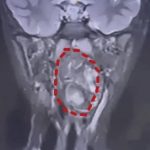

上海复旦大学附属儿科医院近日成功为一名六岁男童,切除一枚藏于其咽喉内的鸡蛋大小肿瘤。经医生诊断,该枚“畸胎瘤”竟是男童未有正常发育的双胞胎兄弟组织。所幸手术成功,男童已基本痊愈。

医生检查后发现情况极为凶险,小亮的口咽腔仅约8厘米,但该枚大小达6.6厘米的肿瘤已占据大部份气道,仅留下一条狭窄缝隙用作呼吸,若不尽快处理,随时有窒息死亡的危险。

为小亮诊治的耳鼻咽喉头颈外科副主任陈超医生解释,该枚肿瘤是由生殖细胞演变而成的“畸胎瘤”。他指出:“我们可以从中看到有脂肪、有软骨。这本应是一对双胞胎,一个正常发育成现在这个人,另一个则可能残留在此处,发育成了畸胎瘤。”